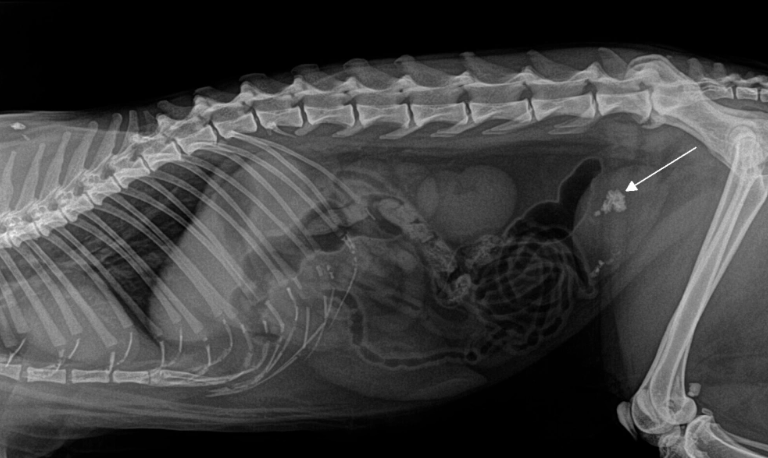

RTG

Rentgenska dijagnostika kao neinvazivna dijagnostička pretraga neophodna je za bolju vizualizaciju koštanog sistema i unutrašnjih organa. Nekada je nužna sedacija pacijenta da bi se mogao bolje pozicionirati za snimanje.